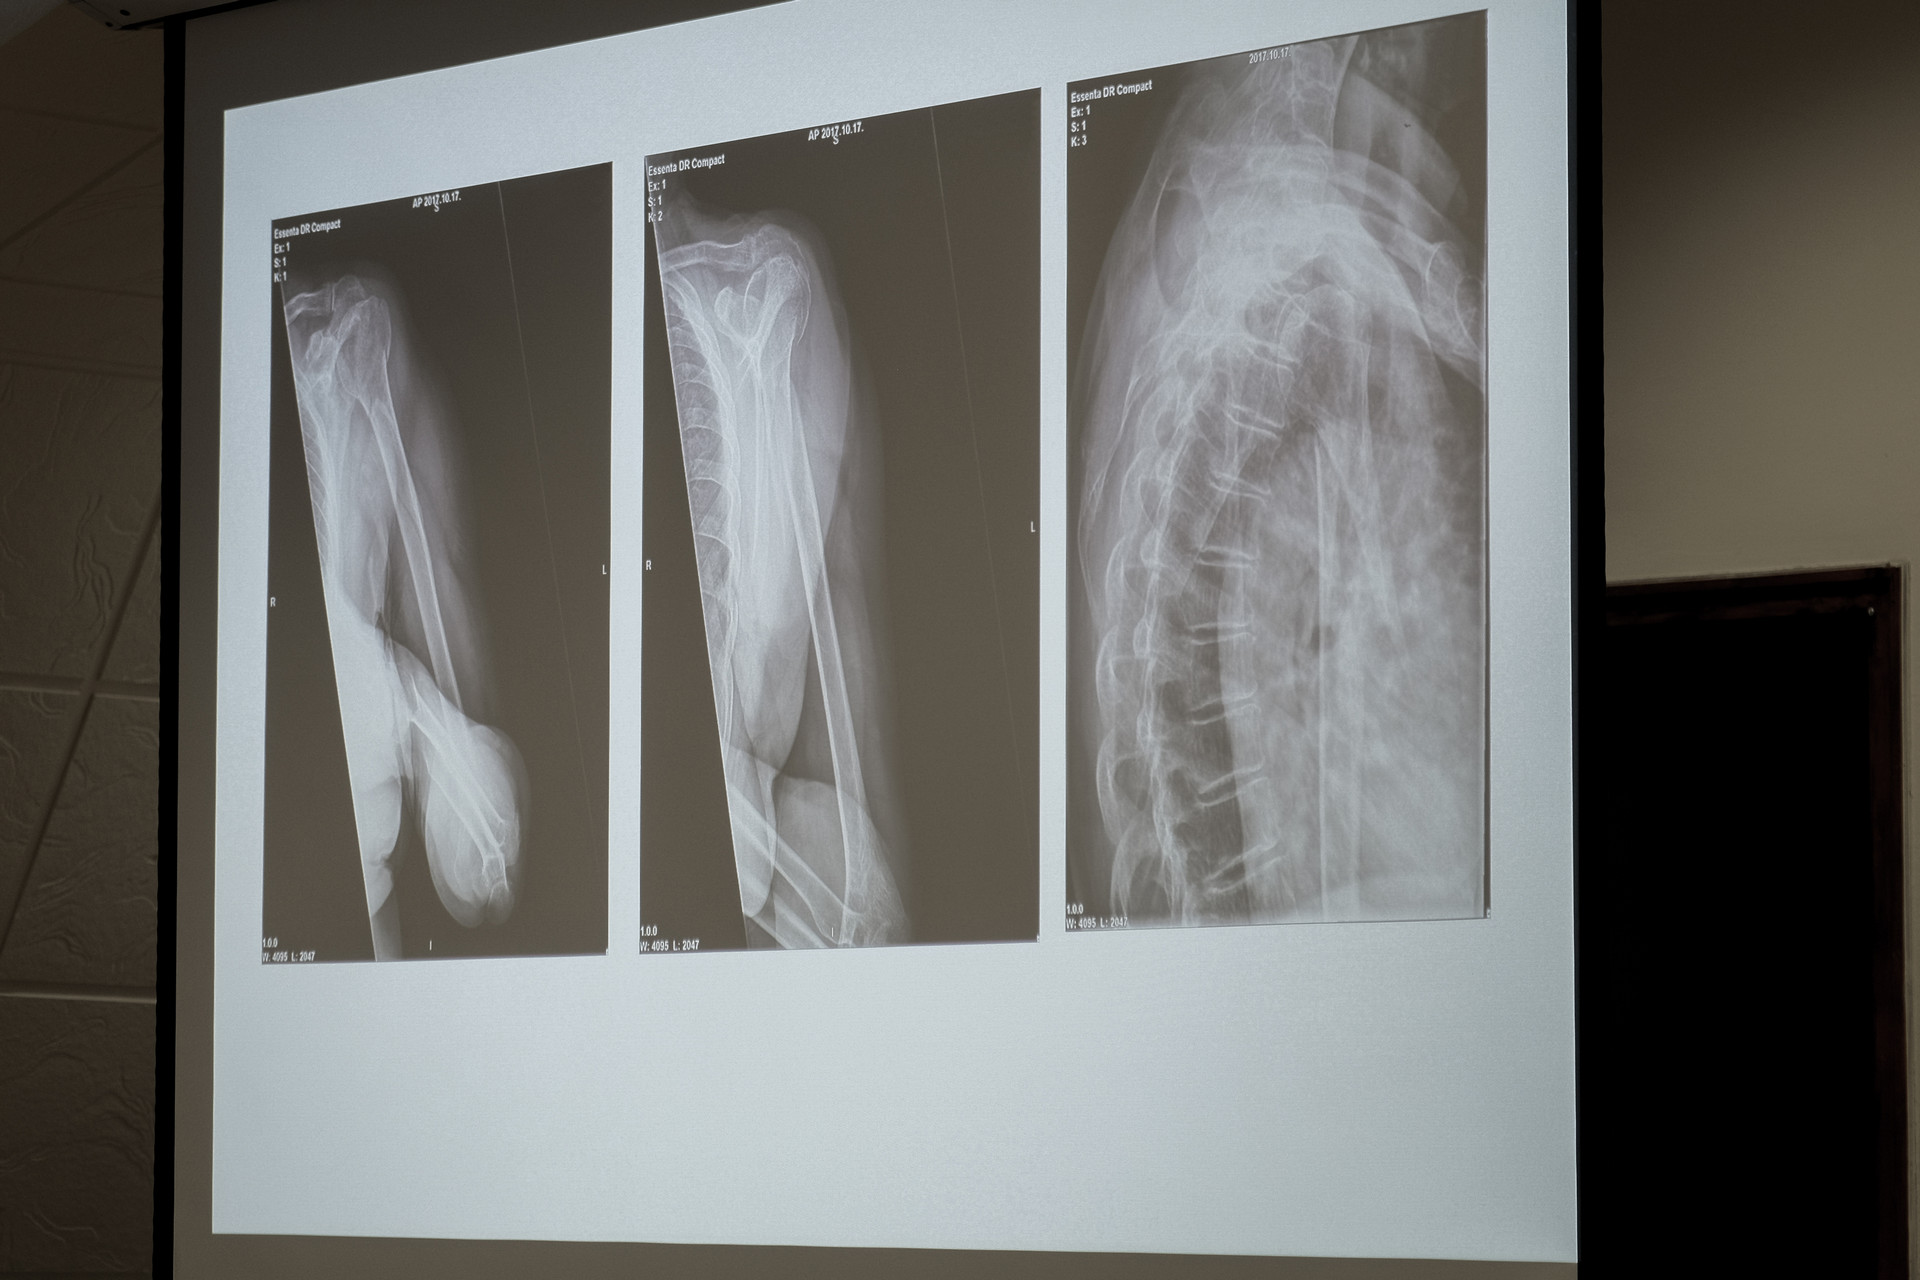

Három műtétet nézhettek meg online a hazai ortopédsebészek a Pándy Kálmán kórház Árvay termében. Az élőben közvetített beavatkozásokhoz a jelenlévők hozzászólhattak, megoszthatták egymással véleményüket. Az első eset egy, a koponyát is érintő törés volt, amit egy 75 éves nő szenvedett el. A sebészeti munka megkezdése előtt a jelenlévők arról fejthették ki véleményüket, hogyan jártak volna el, amennyiben rájuk hárul a gyógyítás feladata.